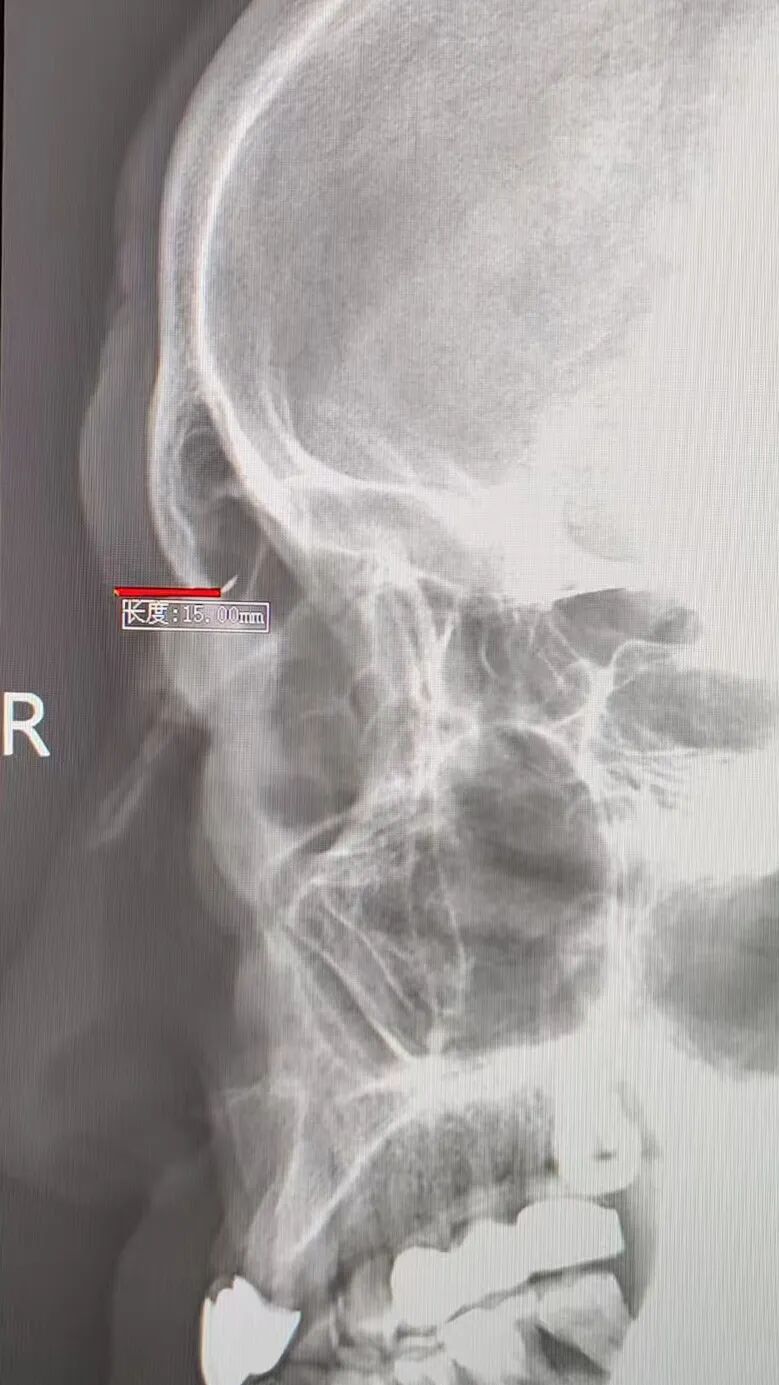

放射科曹俊涛医生接过“定位接力棒”:CT 擅长显示异物与周围组织的毗邻关系,X光片则能精准锁定空间位置。通过头颅正位片+右侧位片的联合检查,他不仅进一步确认了异物位于右眼两点钟方向,更精准测算出异物大小及与眼眶的距离,为手术提供了基础坐标。